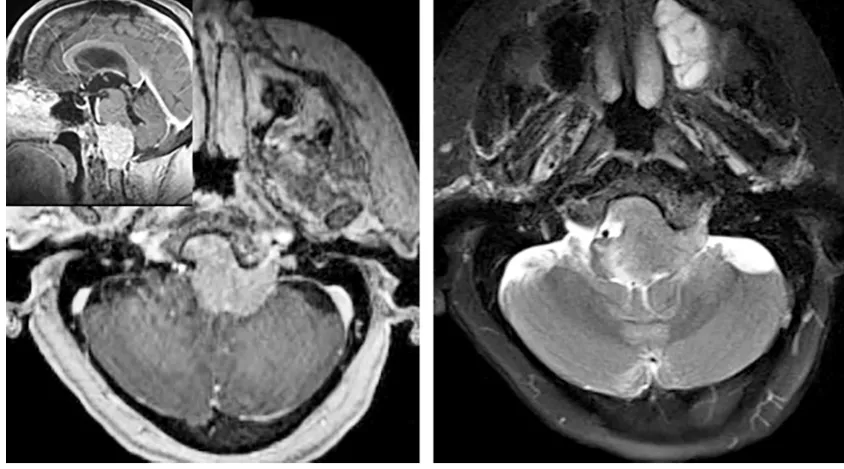

这台手术中,巴教授先行C1左侧半椎板切除术,清除动脉周围软组织,清晰显露椎动脉;全切脑膜瘤后,可见受挤压移位的延髓、双侧椎动脉、左侧小脑后下动脉(PICA)近端及椎动脉汇合部;脑干表面及软膜血管丛保持完整。术后未新增神经功能障碍。

巴教授论文中对该则案例手术操作分享